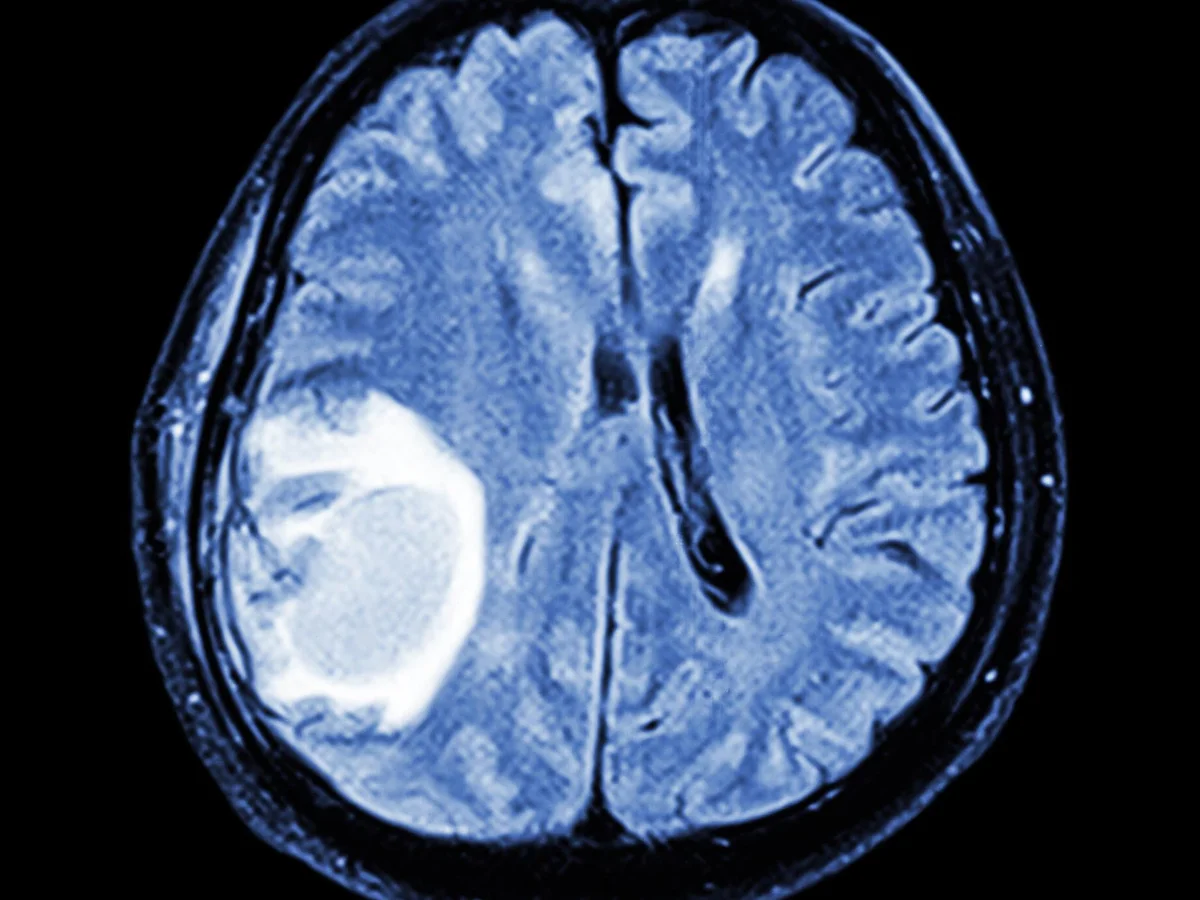

Scientists have unveiled a groundbreaking preliminary atlas charting the intricate development of brain cells from early embryonic stages to adulthood, a significant stride that could revolutionise our understanding of conditions such as autism and schizophrenia. This ambitious research focused primarily on human and mouse brain cells, with additional insights gleaned from monkey tissue. Researchers meticulously mapped the formation, differentiation, and maturation of various cell types, alongside monitoring the dynamic activation and deactivation of genes within them over time. The initial draft has already yielded crucial discoveries, pinpointing key genes that regulate brain processes. It illuminated shared developmental pathways across human and animal brains, while identifying distinct characteristics unique to the human brain, including previously unrecognised cell types. These pivotal findings were detailed in a collection of studies published in Nature and related journals. The research is part of the U.S. National Institutes of Health's BRAIN Initiative Cell Atlas Network, or BICAN, an international scientific collaboration to create a comprehensive atlas of the human brain. "Our brain has thousands of types of cells with extraordinary diversity in their cellular properties and functions, and these diverse cell types work together to generate a variety of behaviours, emotions and cognition," said neuroscientist Hongkui Zeng, director of brain science at the Allen Institute in Seattle and leader of two of the studies. Researchers have found more than 5,000 cell types in the mouse brain. It is thought there are at least that many in the human brain. "The developing brain is an incredibly enigmatic structure because it is hard to access, comprised of so many distinct cell types, and rapidly changing. While we knew the big-picture shifts that happen during brain development, we now have a much more detailed understanding of what the pieces of the developing brain are because of this set of atlases," said UCLA neuroscientist Aparna Bhaduri, another of the research leaders. The research promises important practical applications. "First, by studying and comparing brain development in human and animals, we will better understand human specialisation and where our unique intelligence comes from. Second, by understanding normal brain development in humans and animals, we will be better able to study what changes are happening in diseased brains - when and where - both in human diseased tissues and in animal disease models," Zeng said. By gaining this knowledge, scientists hope to achieve more precise gene and cell-based therapies for a range of human diseases, Zeng said. The hope is that the findings will provide a deeper understanding of autism, attention deficit hyperactivity disorder, schizophrenia and other conditions known to unfold during brain development. The brain regions for which the researchers created atlases for cell type development included the neocortex, which is the part of the brain's outermost layer where higher cognitive function originates, and the hypothalamus, a small structure deep in the brain that helps govern body temperature, blood pressure, mood, sleep, sex drive, hunger and thirst. One study showed that a subset of cells in human brain tumours are similar to embryonic progenitor cells - a kind of cell in the embryo that can change into specific types within a particular brain region - raising the possibility that such tumors may hijack developmental processes to drive malignancy. The researchers identified some unique aspects of the human brain. One example was the prolonged process of differentiation in cortical cell types due to the long period of human brain development from foetus to adolescence compared to the speedier development timeline in the animals. Among the newly identified brain cell types were some in the neocortex and the striatum region, which controls movement and certain other functions. More work is ahead. "The goal is to ultimately understand not only what the pieces of the developing brain are, but also to describe what happens in neurodevelopmental and neuropsychiatric disorders that develop vulnerability during development," Bhaduri said. "This is also relevant to brain cancer, which my lab also studies, as during brain cancer these developmental pieces re-emerge. So it is really a big goal, and it will take time to fully understand and treat all these disorders. But this set of papers is a nice piece of progress," Bhaduri said.